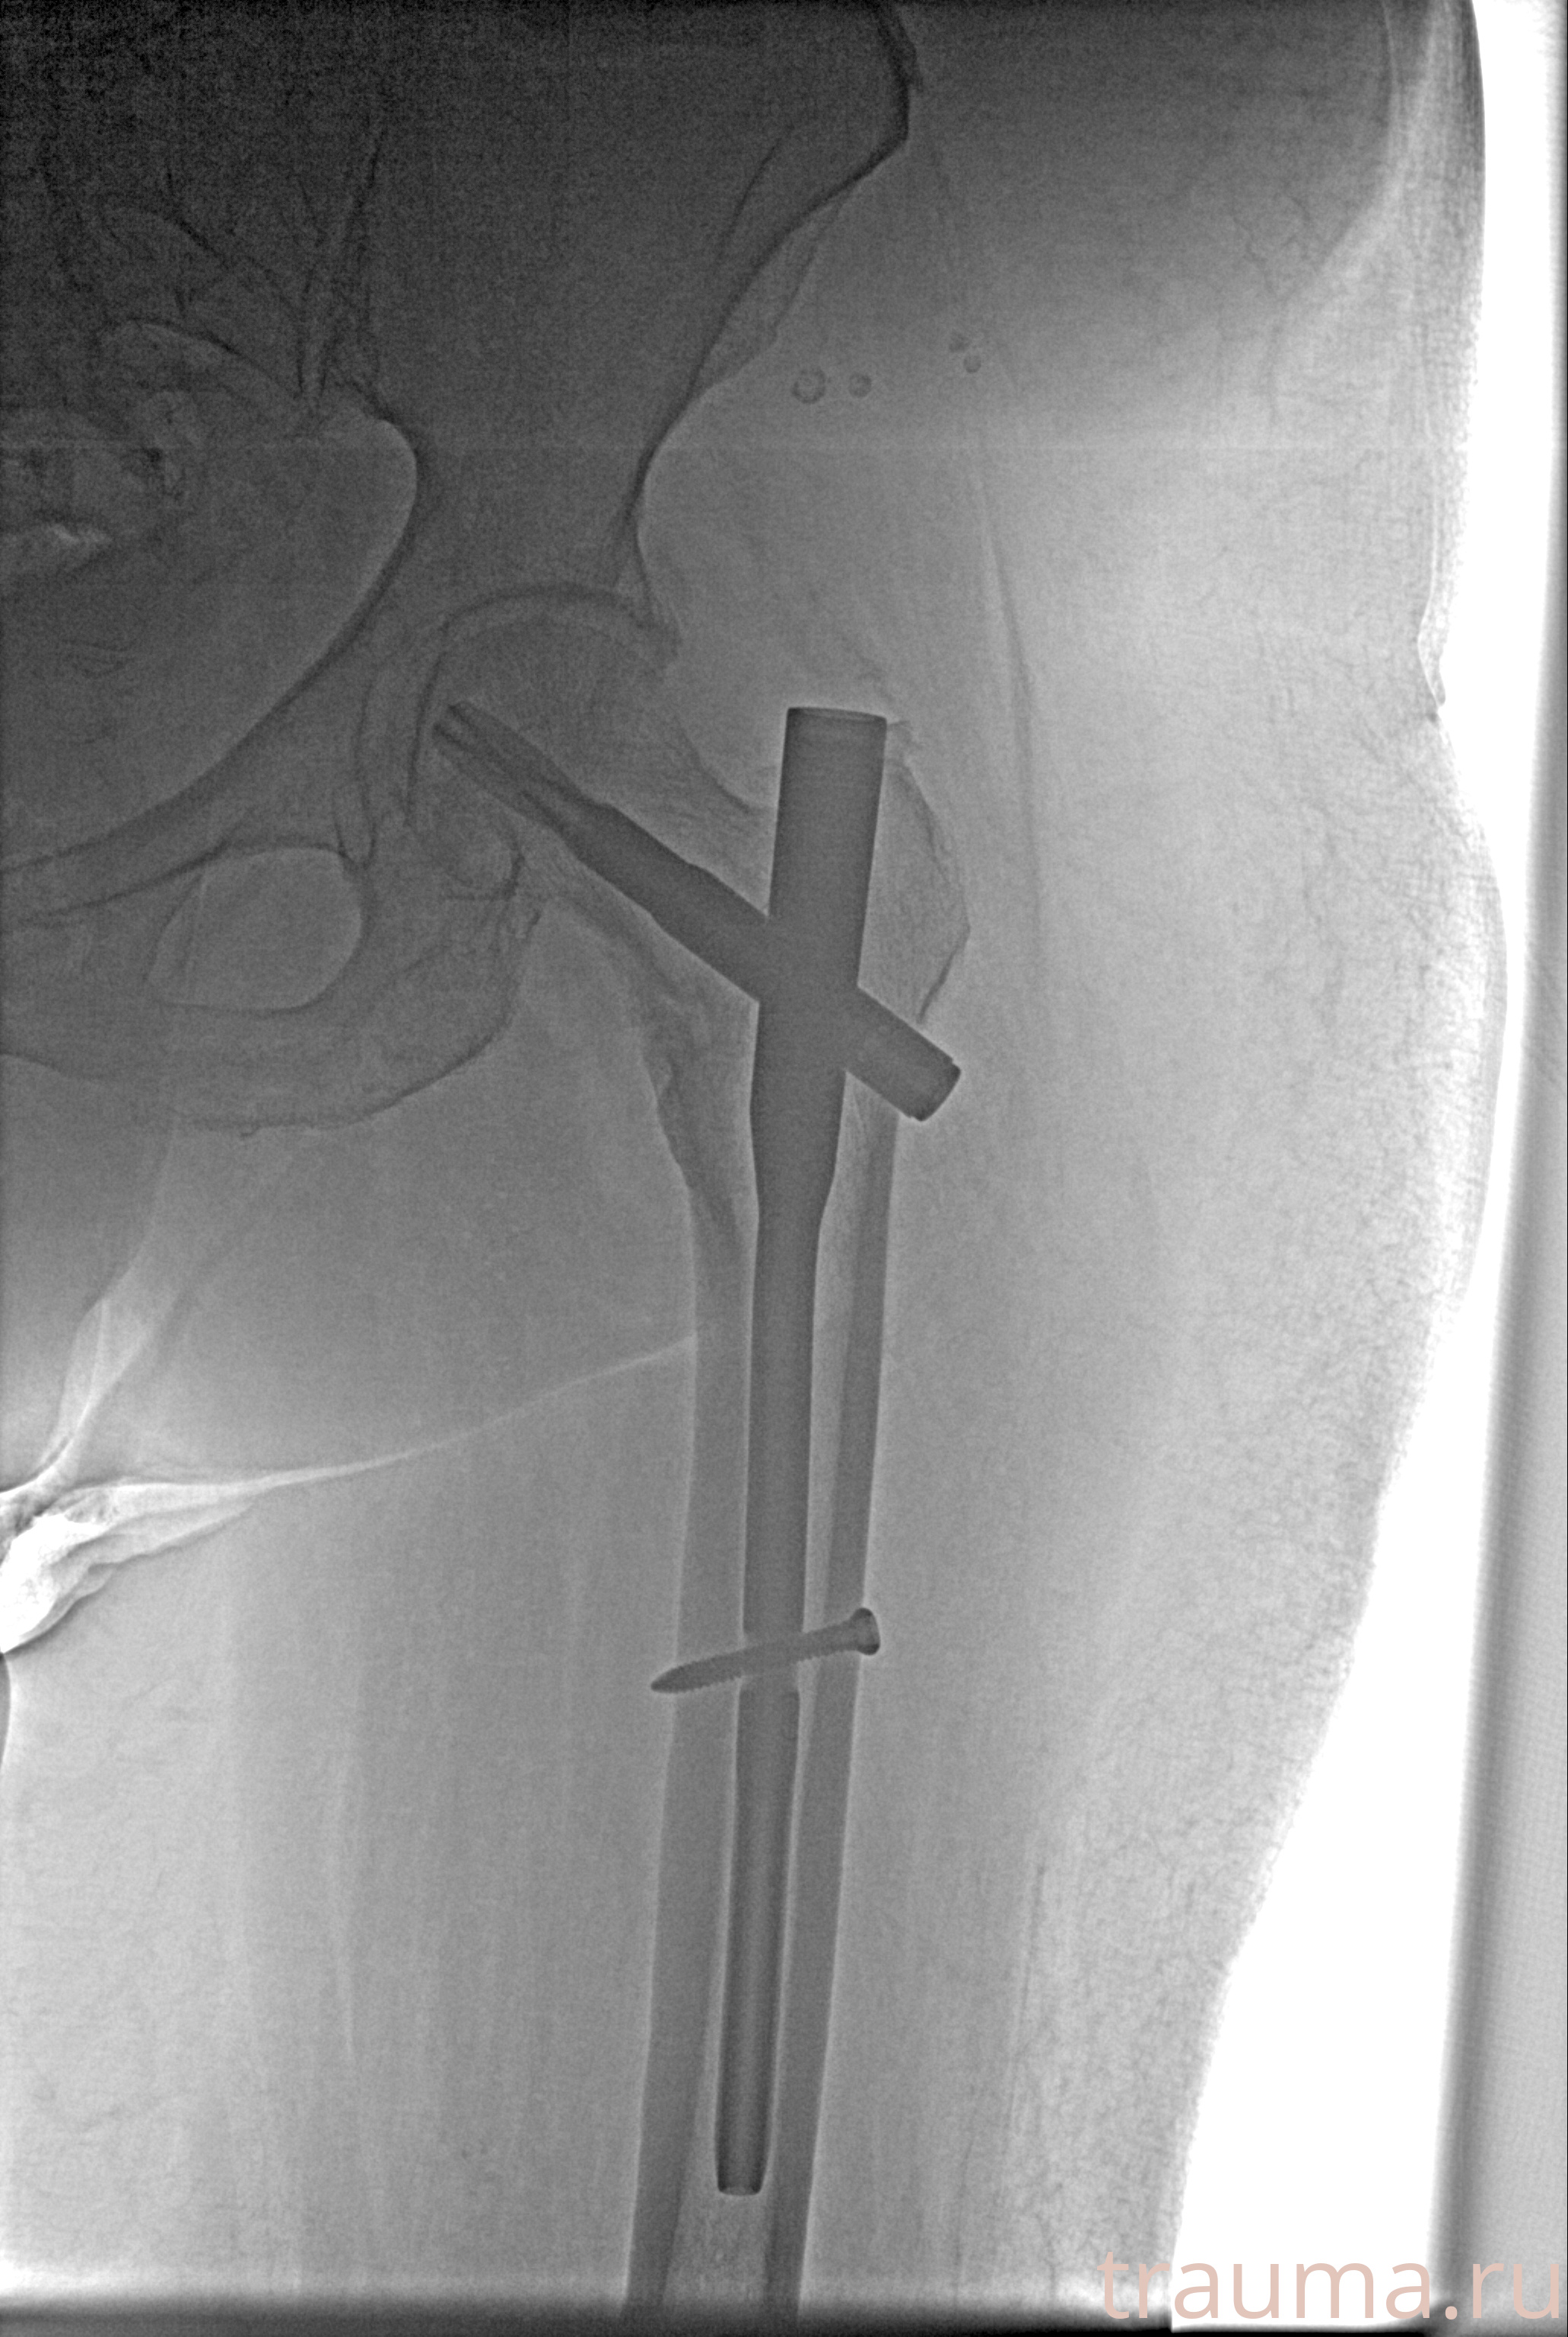

Рентгенограммы